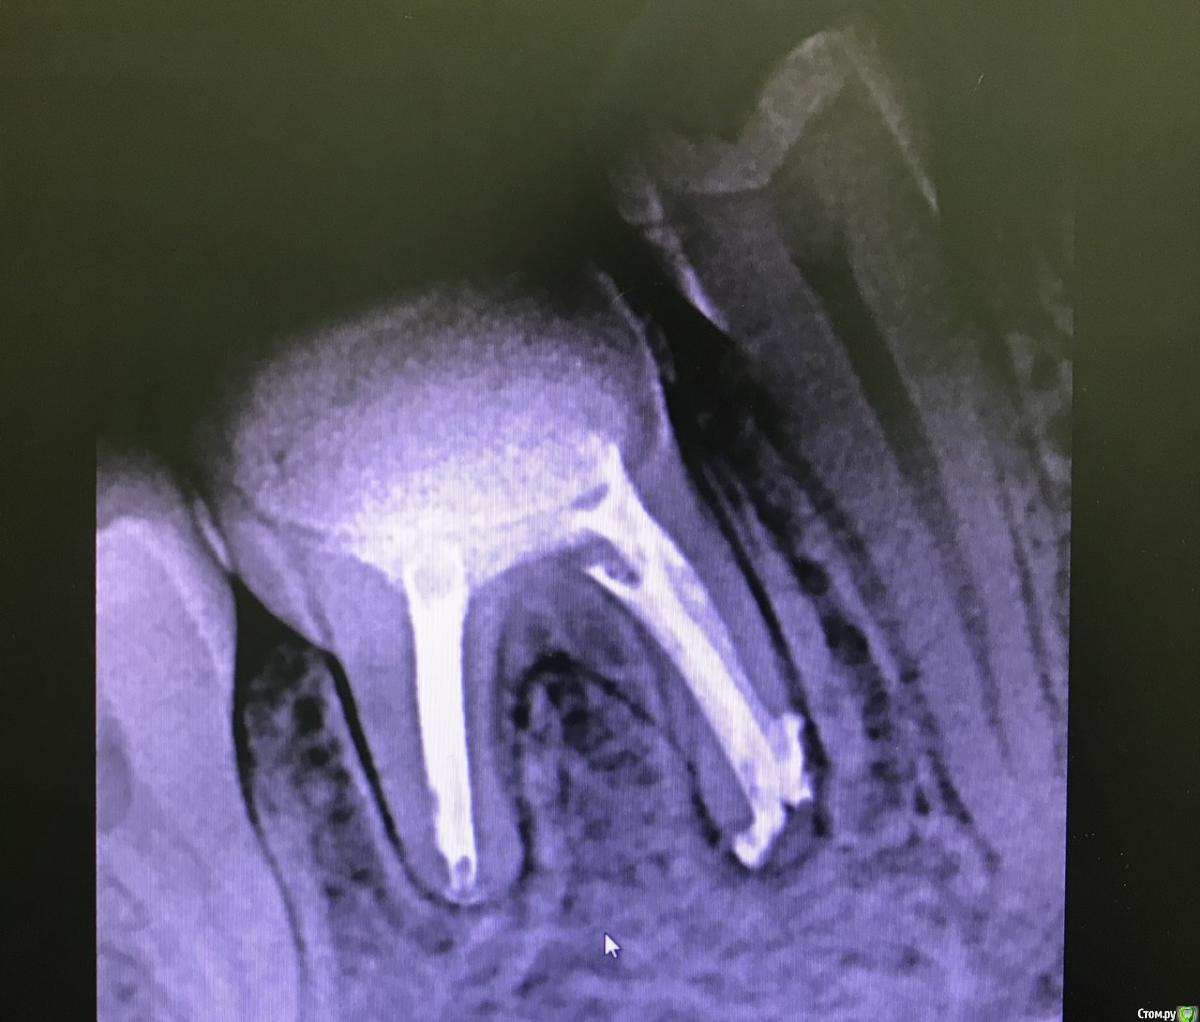

В последний раз мне снова поставили кальций, временную пломбу и отпустили на 2 недели. Острая боль прошла, но зуб все равно как бы "напоминал" о себе небольшой ноющей болью, но дискомфорта это не приносило. Через  2 недели я сообщила все свои ощущения врачу, мне снова промыли, установили гуттаперчевые штифты и временную пломбу. Меня немного смутило, что поставили штифты с временной пломбой, и пломба почти сразу отвалилась, и мои очень тонкие стенки зуба были оголены. Через неделю поставили  световую пломбу, которая была очень огромной в плане высоты. Я боялась, что стенка зуба от такого давления может лопнуть и снова пошла к врачу, чтобы она спилила ее.

Прикрепляю рентген до, 3 рентгена после первого лечения, рентген после установки гуттаперчевых штифтов. Также есть КТ до перелечивания, вдруг кто-то заинтересуется.

Добрый день. По снимкам  после все в пределах нормы.